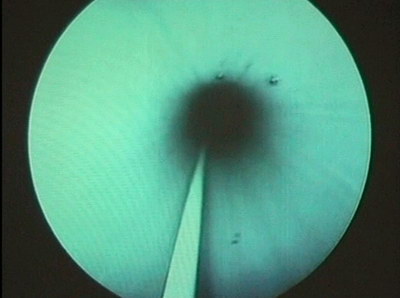

Доступ бужирован до 30 F. Нефропиелоскопия по кожуху № 28

F.

Камни подвергнуты трипсии ультразвуковым методом. Удалено

9 конкрементов монолитом, остальные литолапаксией. ЛМС почки